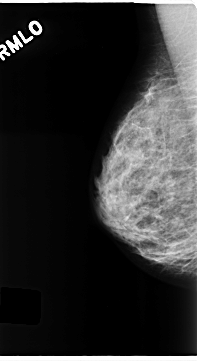

C_0199_1.RIGHT_MLO

RIGHT_MLO LINES 4688 PIXELS_PER_LINE 2560 BITS_PER_PIXEL 12 RESOLUTION 50 NON_OVERLAY